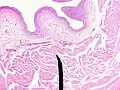

Microanatomy

When viewed under a microscope the bladder can be seen to have an inner lining (called epithelium), three layers of muscle fibres, and an outer adventitia.[6]

The inner wall of the bladder is called urothelium, a type of transitional epithelium formed by three to six layers of cells; the cells may become more cuboidal or flatter depending on whether the bladder is empty or full.[6] Additionally, these are lined with a mucous membrane consisting of a surface glycocalyx that protects the cells beneath it from urine.[12] The epithelium lies on a thin basement membrane, and a lamina propria.[6] The mucosal lining also offers a urothelial barrier against the passing of infections.[13]

These layers are surrounded by three layers of muscle fibres arranged as an inner layer of fibres orientated longitudinally, a middle layer of circular fibres, and an outermost layer of longitudinal fibres; these form the detrusor muscle, which can be seen with the naked eye.[6]

The outside of the bladder is protected by a serous membrane called adventitia.[6][14]